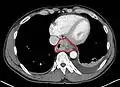

Esophageal cancer (lower part) as a result of Barrettʼs esophagus

Additional testing is needed to assess how much the cancer has spread (see § Staging, below). Computed tomography (CT) of the chest, abdomen and pelvis can evaluate whether the cancer has spread to adjacent tissues or distant organs (especially liver and lymph nodes). The sensitivity of a CT scan is limited by its ability to detect masses (e.g. enlarged lymph nodes or involved organs) generally larger than 1 cm.[41][42] Positron emission tomography is also used to estimate the extent of the disease and is regarded as more precise than CT alone.[43] Esophageal endoscopic ultrasound can provide staging information regarding the level of tumor invasion, and possible spread to regional lymph nodes.